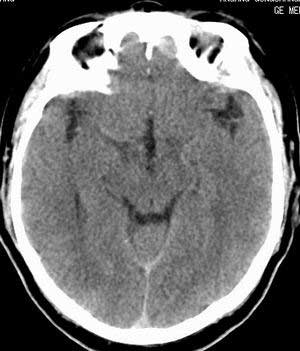

双侧乳突蜂房密度呈气体样,慢性乳突炎可能性不大,

双侧颞叶脑实质密度均匀未见异常密度灶,

考虑颅内未见异常。

条状高密度为小脑幕吧

条状高密度为小脑幕